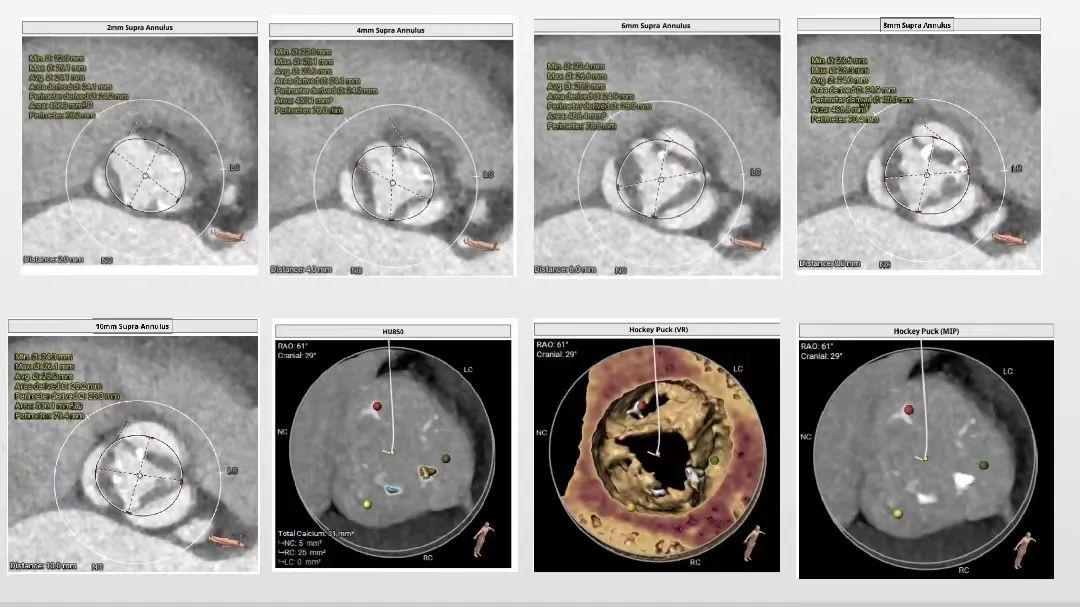

术前评估:

1. 主动脉瓣瓣环周长78.6mm,平均周长径25mm;

2. 功能型型二叶式主动脉瓣,R-L纤维融合嵴,瓣叶增厚,左室流出道开口呈直筒状;

3. 左右冠开口高度可,瓣叶冗长,左、右冠瓣叶长度>瓣叶附着缘到冠脉开口距离;

4. 瓦式窦内径、窦管交界内径可,升主动脉轻微扩张;

5. 主动脉瓣环与水平夹角62°,横位心,主动脉弓距及弓部夹角尚可;

主动脉根部评估:

瓣环上解剖结构评估: